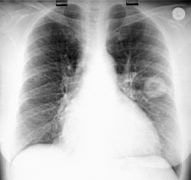

| Eager to broaden our minds, Diana and I sought a foreign elective during our residency training. Her internal medicine program offers an exchange with Uganda, but radiology training there would not be very useful. With the help of Dr. Ken Magnus and his counterparts abroad, Drs. Steve Beningfield, Bongani Mayosi and Dick Pitcher, and about a year of red tape, we arranged a joint elective in Cape Town, South Africa. A month of radiology in Groote Schuur hospital for me, and a month of internal medicine for Diana at nearby New Somerset Hospital. We were lucky to get the same 4-week block in the same city, and 4 weeks holiday each afterward, especially at the perfect time to travel in South Africa, February-April, when Christmas crowds have dwindled, the sun is a little cooler and the rains have not yet come. Not a bad couple of months to get out of Edmonton's winter cold and snow into a place nearly everyone told us is the most beautiful city in the world.